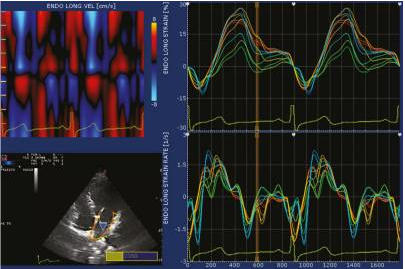

Non-Doppler 2D strain imaging is an innovative technique used to measure strain and strain rate values. This method involves analyzing motion patterns by tracking natural acoustic markers known as speckles in 2D grayscale images. The speckles are formed due to the interference of ultrasound beams in the myocardium, and they serve as inherent acoustic markers that can be tracked frame by frame. This tracking process allows for the quantification of myocardial deformation and provides valuable insights into the mechanics and function of the heart. [53], [54] The use of non-Doppler 2D strain imaging represents a significant advancement in cardiac imaging techniques.

Speckle tracking echocardiography (STE) utilizes an automatic measurement technique that assesses the distance between speckles, enabling angle-independent strain measurement. This method allows for simultaneous measurements from multiple regions within an image plane, as depicted in [Figure 7]. In contrast, Doppler-based strain measurements rely on calculating velocities between a fixed point and a reference point, typically an external probe.

STE provides a direct measure of strain by analyzing the distance between two points within a specific region of the myocardium. In contrast, tissue Doppler imaging (TDI) calculates strain by integrating strain rate (SR) measurements. [55], [56], [57] The use of speckle tracking in STE offers advantages over TDI, as it allows for a more comprehensive and direct assessment of myocardial strain.

STE offers significant advantages, particularly its independence from ultrasound angle and translational motion of the heart within the chest. These features enable the measurement of circumferential and radial strains from the left ventricular (LV) short axis, as well as longitudinal strain from apical myocardial regions. Additionally, STE holds promise for measuring LV rotation and torsion, further enhancing its capabilities in assessing myocardial mechanics. [56], [57], [58]

While higher frame rates are necessary for measuring peak velocities and strain rates, optimal frame rates of around 80 frames per second are typically sufficient. STE finds clinical application in evaluating regional ventricular and atrial myocardial function, as well as in assessing atrial and ventricular dyssynchrony. Its versatility in assessing various aspects of cardiac function makes it a valuable tool in clinical practice.